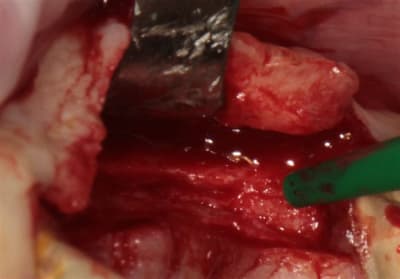

OK nous n'y sommes pas encore, mais je me suis fais une petite intervention sympa ce matin, avec un nouvel outil (qui n'est pas sur les photos ....because chut!) qui devrait permettre de simplifier la pratique de l'expansion, afin que tout un chacun puisse pratiquer ce sport sympa, et si tout va bien je pourrais vous en parler (peut être) en Juin.

crête en lame d'1 mm..pour 23/24/26

Axioms 3.4 x10 (2) et 3.4x 8